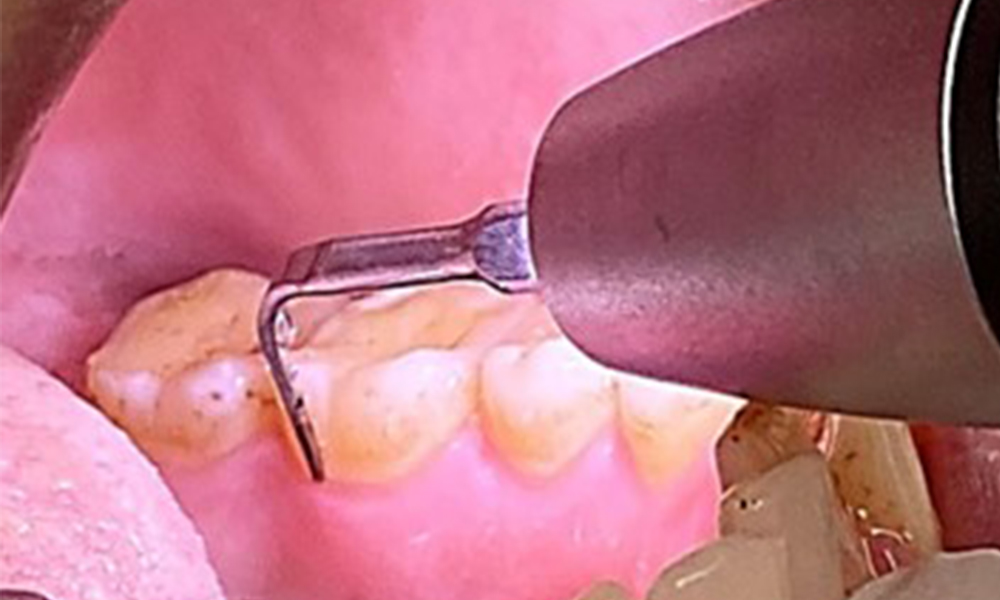

The objective would be to control disease risk by removing supragingival and subgingival biofilm. The instruments can be selected based on patient needs. First, calculus and any concretions must be removed using ultrasonic and/or manual instruments (Fig. 10).